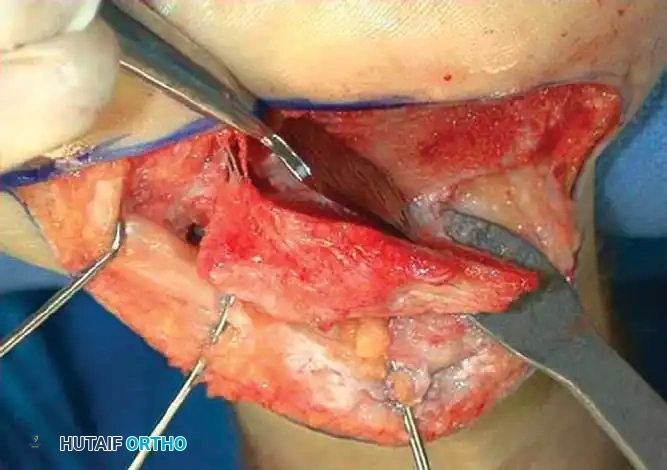

1. Lateral Exostectomy and Decompression

For Type I malunions, the primary issue is lateral impingement.

Intraoperative view demonstrating exposure of the lateral calcaneal wall and preparation for exostectomy.

An extensile lateral approach is utilized to elevate the full-thickness fasciocutaneous flap. The sural nerve and peroneal tendons are identified and protected. The hypertrophic lateral wall of the calcaneus is resected using an osteotome or oscillating saw, thoroughly decompressing the subfibular space.